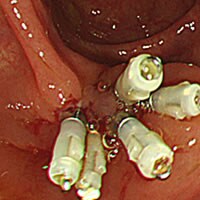

大腸ポリープ切除

診断から治療まで一貫して対応ができるため、検査の際に万が一、ポリープを発見した際には即日の切除手術を行うことも可能です。

内視鏡での観察中に大腸ポリープが見つかることがありますが、ポリープを速やかに切除することに

なった場合、少し検査時間が延長されますのでご了承ください。

(ポリープ1個の切除に、5~10分の時間を要します)検査終了後